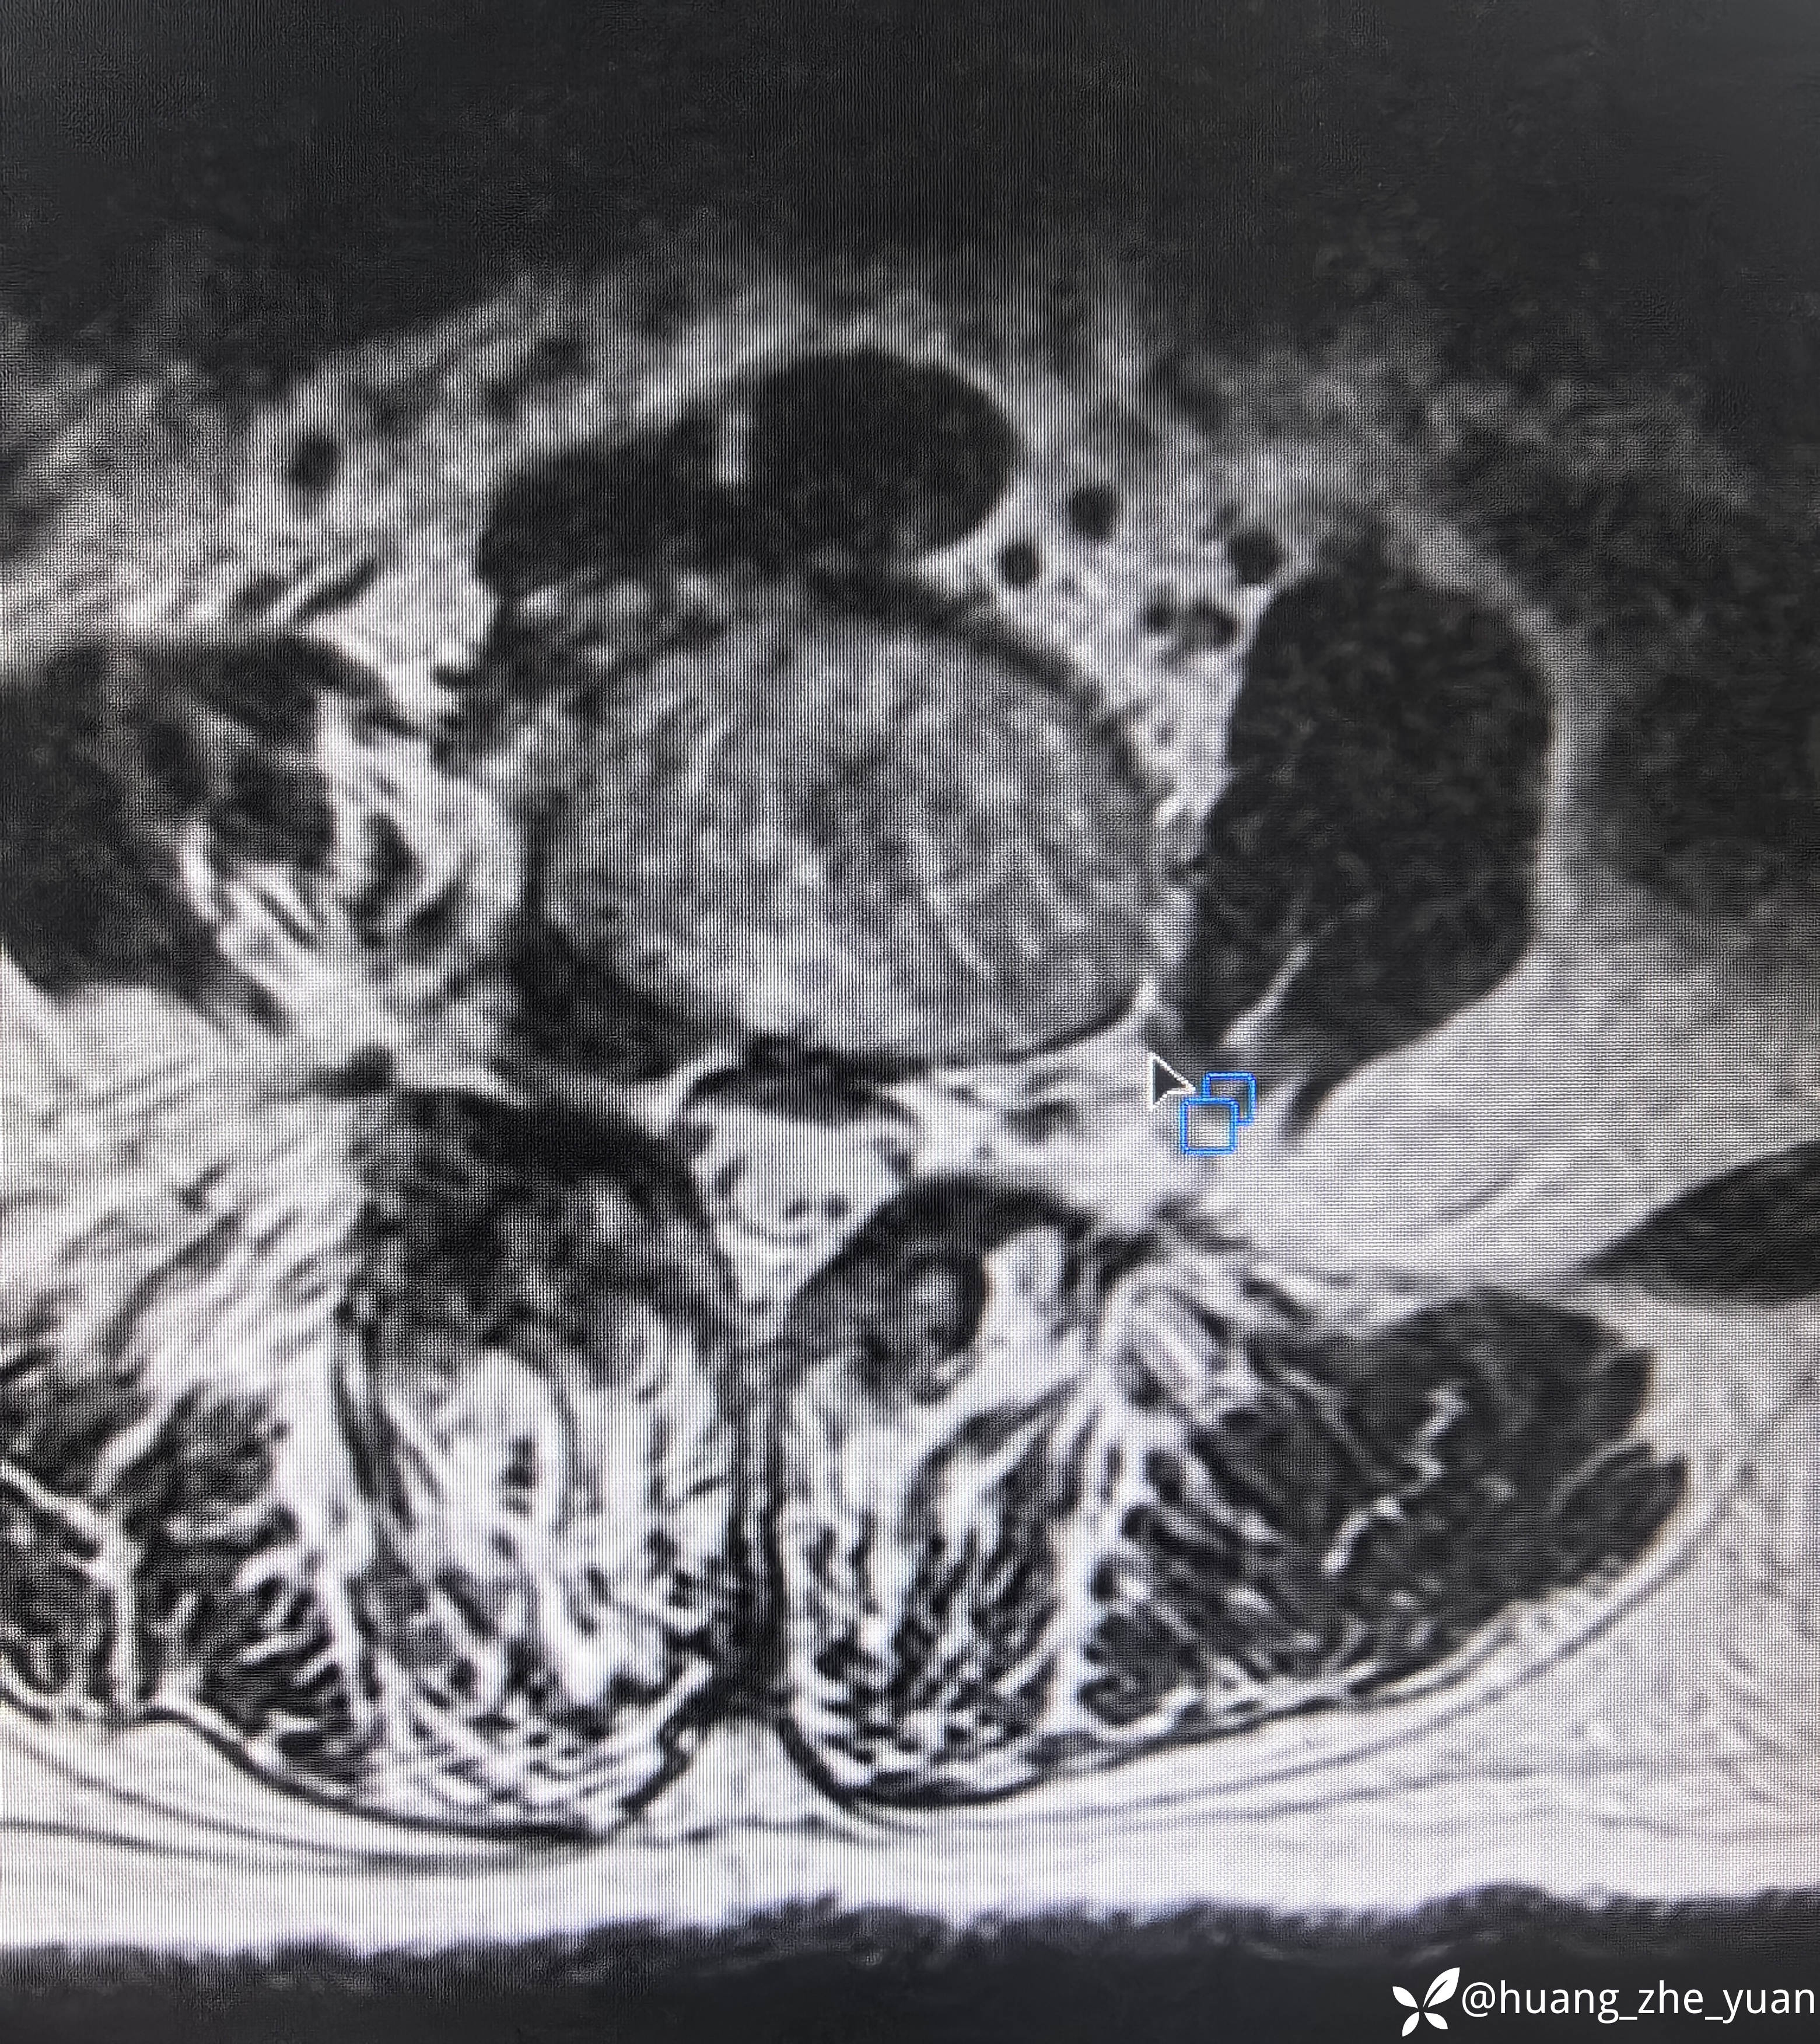

70岁女性,反复右下肢放射痛八个月。合并症:糖尿病,胰岛素泵控制。